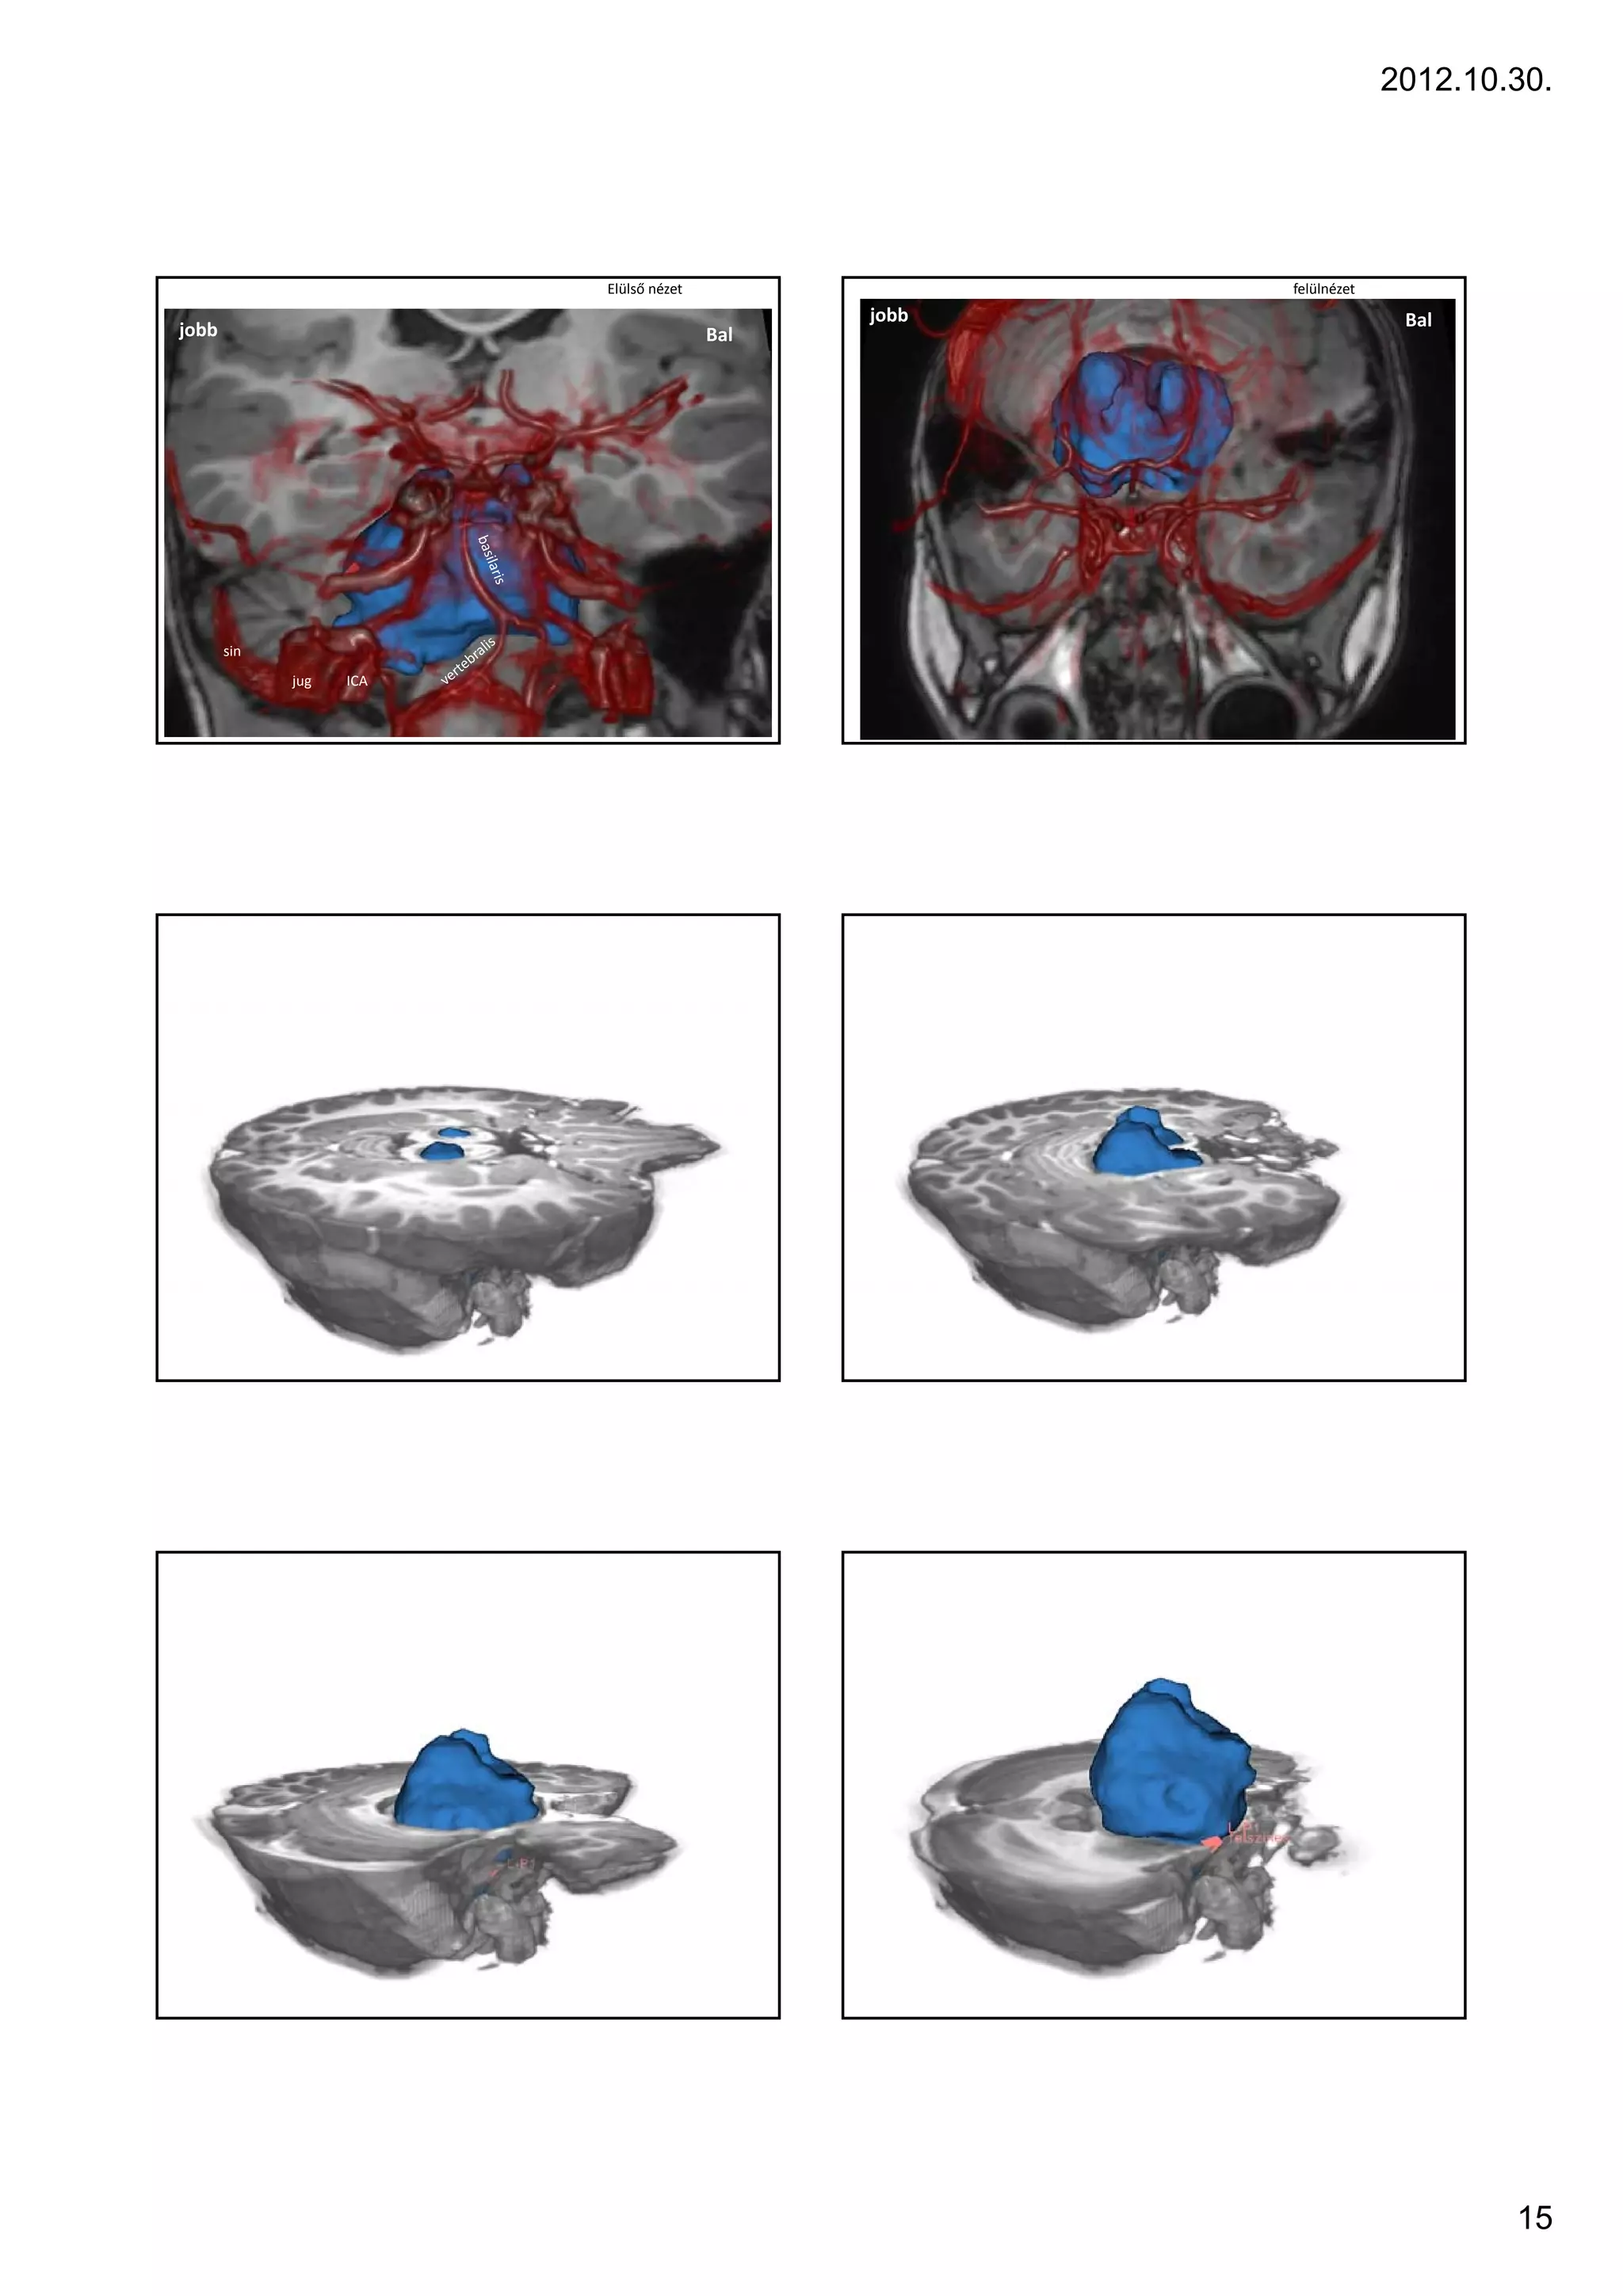

Elülső nézet                felülnézet

jobb                                    Bal

sin

jug   ICA

2012.10.30. Elülső nézet felülnézet jobb Bal jobb Bal sin jug ICA 15